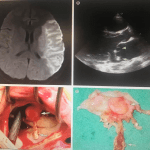

Nei giorni delle nevicate che hanno messo in ginocchio l’Italia, la fotografia dei pronto soccorso degli ospedali “Maggiore”, “Sant’Orsola” e “Rizzoli” di Bologna ma anche della Usl Imola, era sempre la stessa: aumento degli accessi per le emergenze urgenze, poco personale e situazioni di stress che sono sfociate, in alcuni casi gravi, nelle aggressioni al personale medico e infermieristico. E la questione sicurezza, alla pari di quella del demansionamento, diventa oggetto di attenzione da parte della Fials, il primo sindacato nei quattro presidi citati, per rappresentanza sindacale aziendale. Sepe lo ribadisce quando punta il dito sulle dotazioni organiche non sufficienti: “Il nostro sindacato – spiega – non ha firmato il piano di assunzioni della Usl Bologna che invece è stato sottoscritto da Cgil, Cisl e Uil”. Una posizione fuori dalla triplice non per questioni pregiudiziali, ma per un dato di fatto: “Se quel piano di assunzioni è giusto – ragiona Sepe – perché ci sono ancora infermieri che fa i doppi turni o a maturato ferie dal 2014?”.

A giudizio del segretario provinciale Fials, c’è una contraddizione raccontata dai numeri: “Se un infermiere matura 3000 ore di straordinario significa che servono almeno un paio di assunzioni in quell’azienda”. Esempio plastico di una situazione critica, esplosa nei giorni dell’emergenza neve e ghiaccio: “Ma l’Azienda sanitaria – commenta Sepe – deve prevedere le situazioni di emergenza urgenza anche quando ci sono i picchi influenzali” e i pronto soccorso vengono presi d’assalto. Con lunghe attese e un livello di tensione che sfocia in vere e proprie aggressioni. In un video appello, postato sul suo profilo facebook, Sepe chiede maggiore sicurezza nei pronto soccorso: la presenza di una guardia giurata, 24 ore al giorno, potrebbe funzionare da deterrente, anche se in certi casi servirebbe un poliziotto.